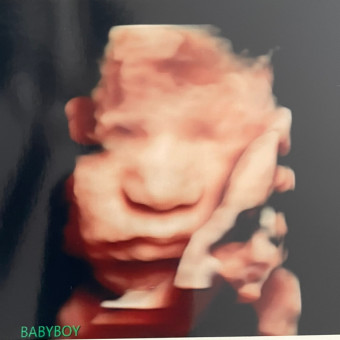

Baby Peregil Shower By Mail

Shayna & Bobby Peregil

Pearland, TX

January 20, 2026